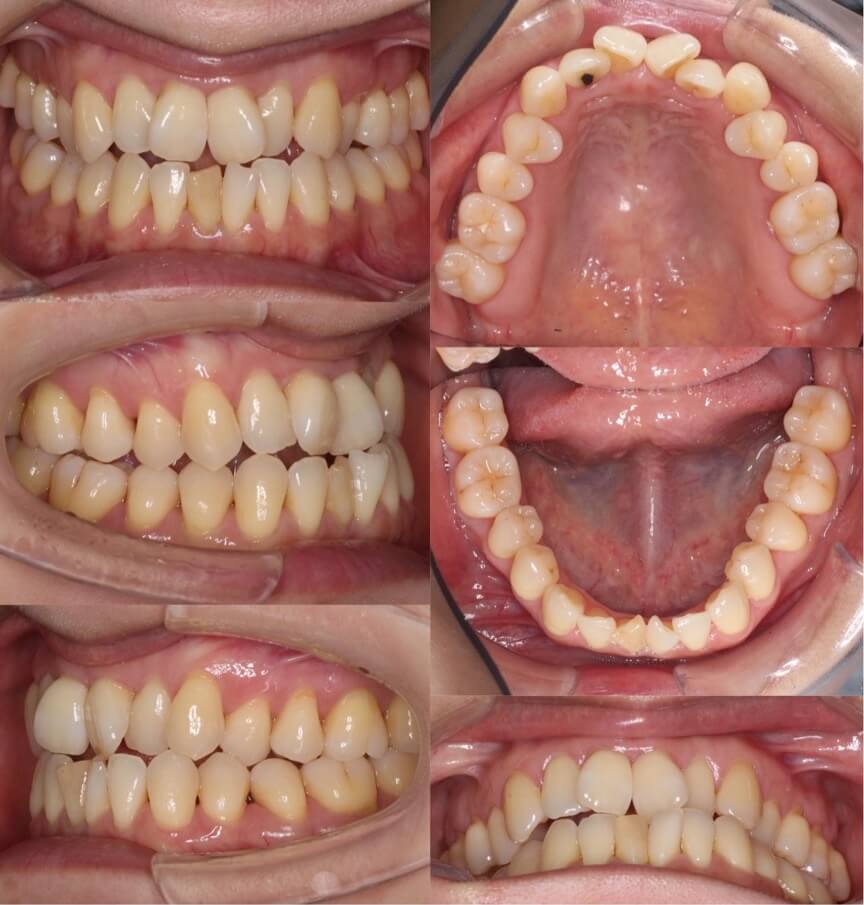

40歳女性・マウスピース型矯正装置

<症例概要>

主訴:クロスバイト

年齢・性別:41歳女性

住まい:千葉県浦安市

症状:下顎左偏・交叉咬合・上下顎前歯捻転・正中線の不一致

治療方針:右下臼歯後方移動・IPR・上顎歯列拡大

治療装置:マウスピース型矯正装置(アライナー装置)

治療期間:1年9か月

アライナー枚数:52+25+14(7日交換)

リテーナー:上下フィックスタイプ+クリアタイプ

治療費用:990,000(税込)

代表的副作用:痛み・治療後の後戻り・歯根吸収・歯髄壊死・歯肉退縮

下あごに非対称により奥歯のクロスバイトになっており、かみ合わせが安定していません。また、全体的にあ歯茎も下がってきています。矯正治療後は、歯茎に少し退縮がみられますが、上下の正中線は一致し前歯のかみ合わせは安定しました。